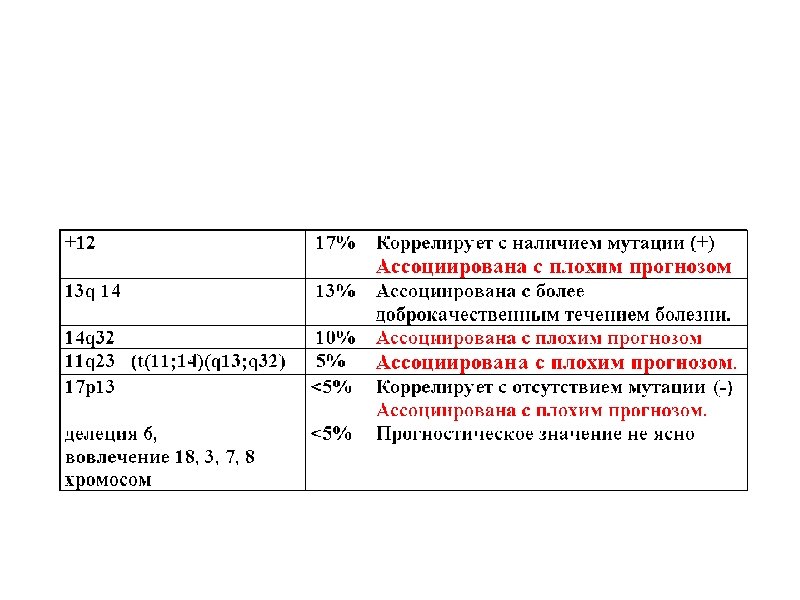

Время удвоения лимфоцитов менее 6 месяцев Время удвоения лимфоцитов более 6 месяцев Стадия на момент диагноза III – IV / C (Rai / Binnet) Возраст менее 65 лет I – II / A Возраст более 65 лет ZAP-70 < 20% Соматическая мутация (-) Соматическая мутация (+) 17 p делеция (p 53 мутация), 13 q делеция 11 q делеция, 12 q трисомия CD 38 (+) CD 38 (-)